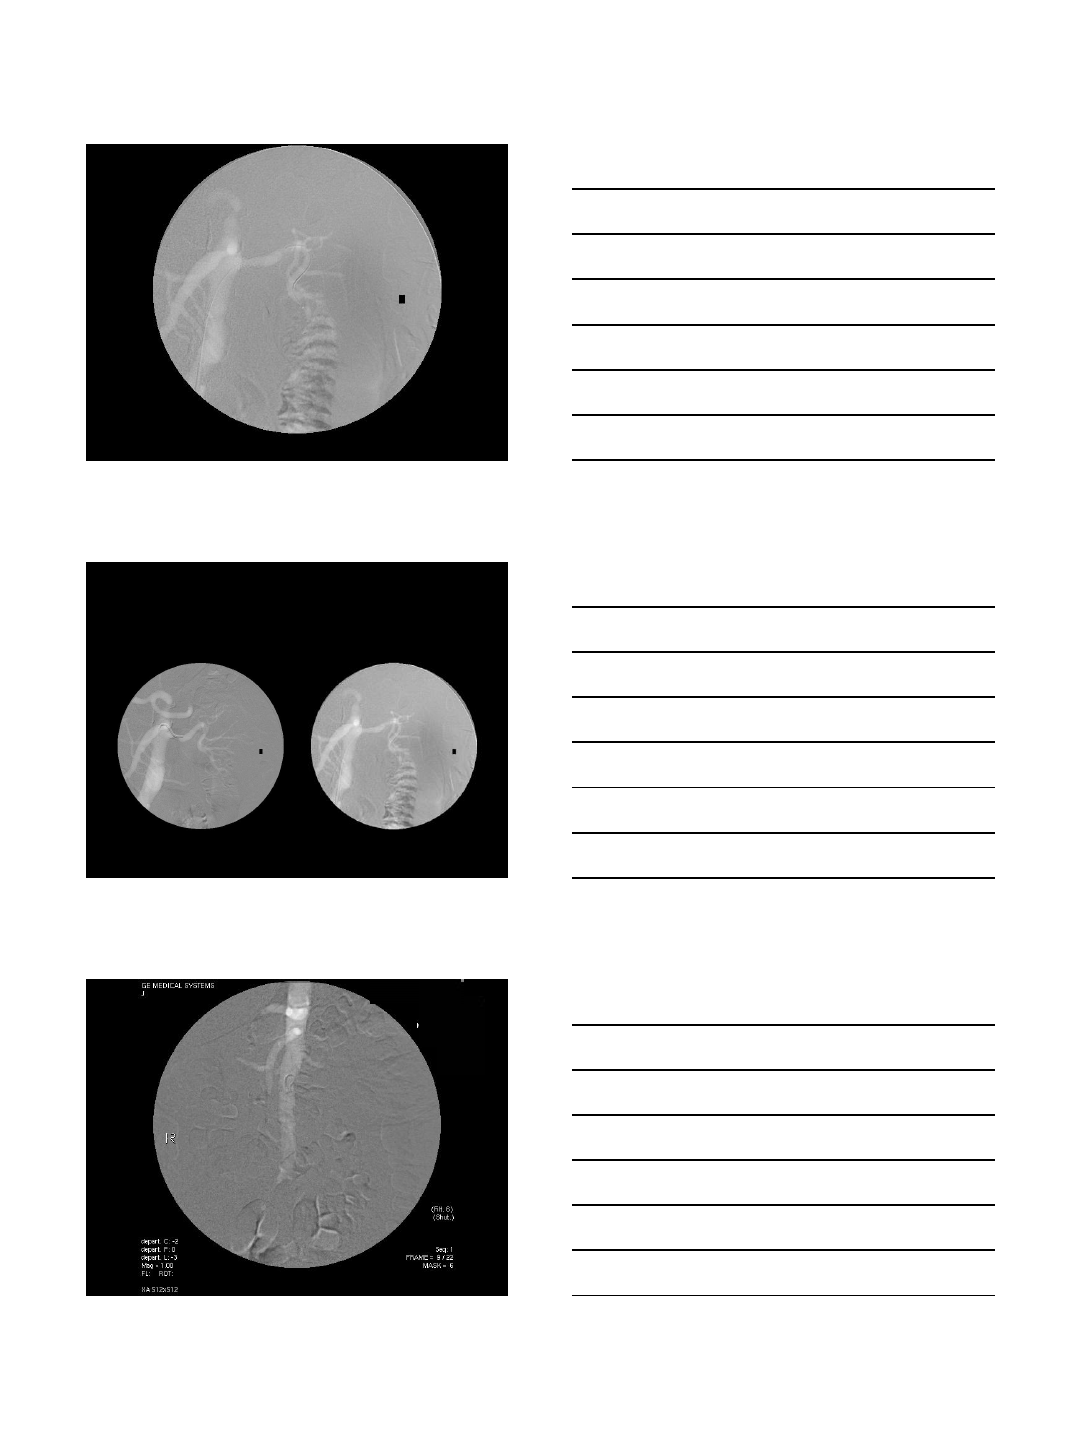

DIALYSIS ACCESS INTERVENTION

Case Presentation

•68 year old woman with ESRD

•On hemodialysis via an AV fistula

•Allergic to iodinated contrast

•Refractory to pre-medication

•Ongoing problems with her AV fistula

•Bleeding post-dialysis

•Requires 3 month-surveys

CO2 Fistulogram

•This patient’s procedures are

completed whenever necessary without

the use of contrast medium

•No further allergic reactions